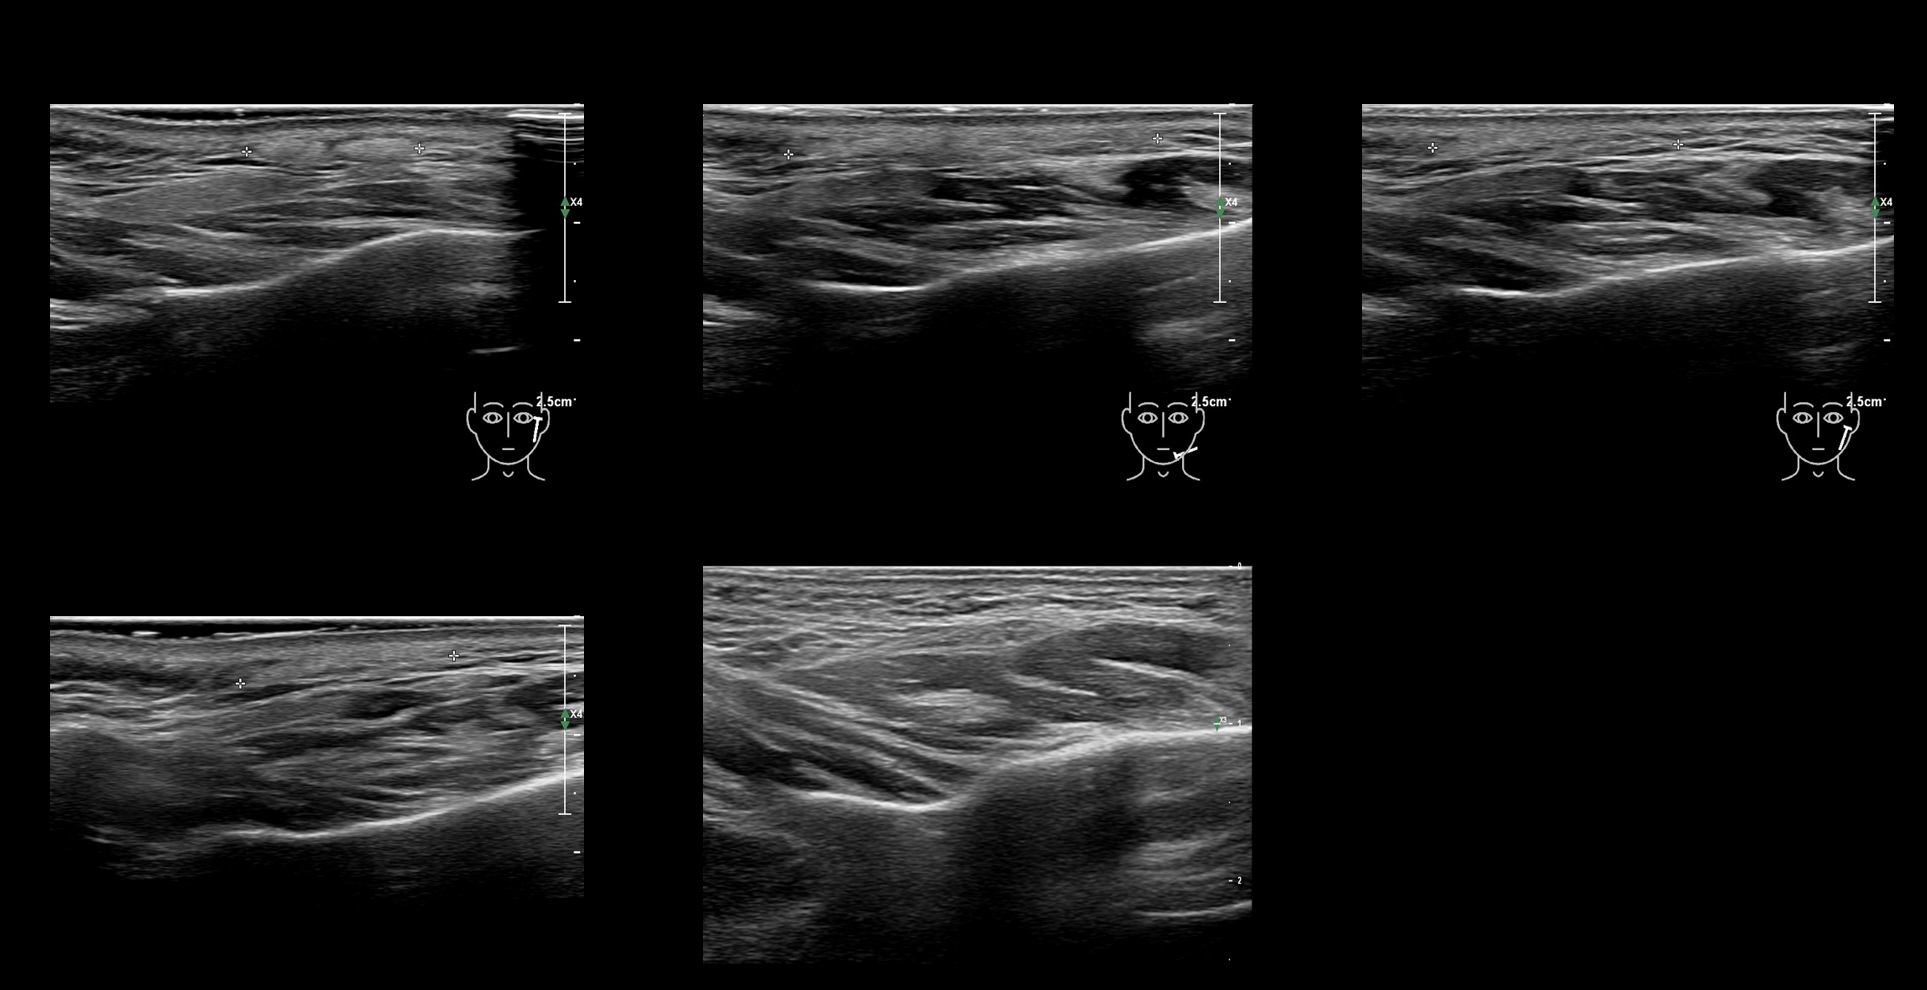

Draw in the second image below where the fillers are located. To check if your answer is correct, swipe the first image to the right.